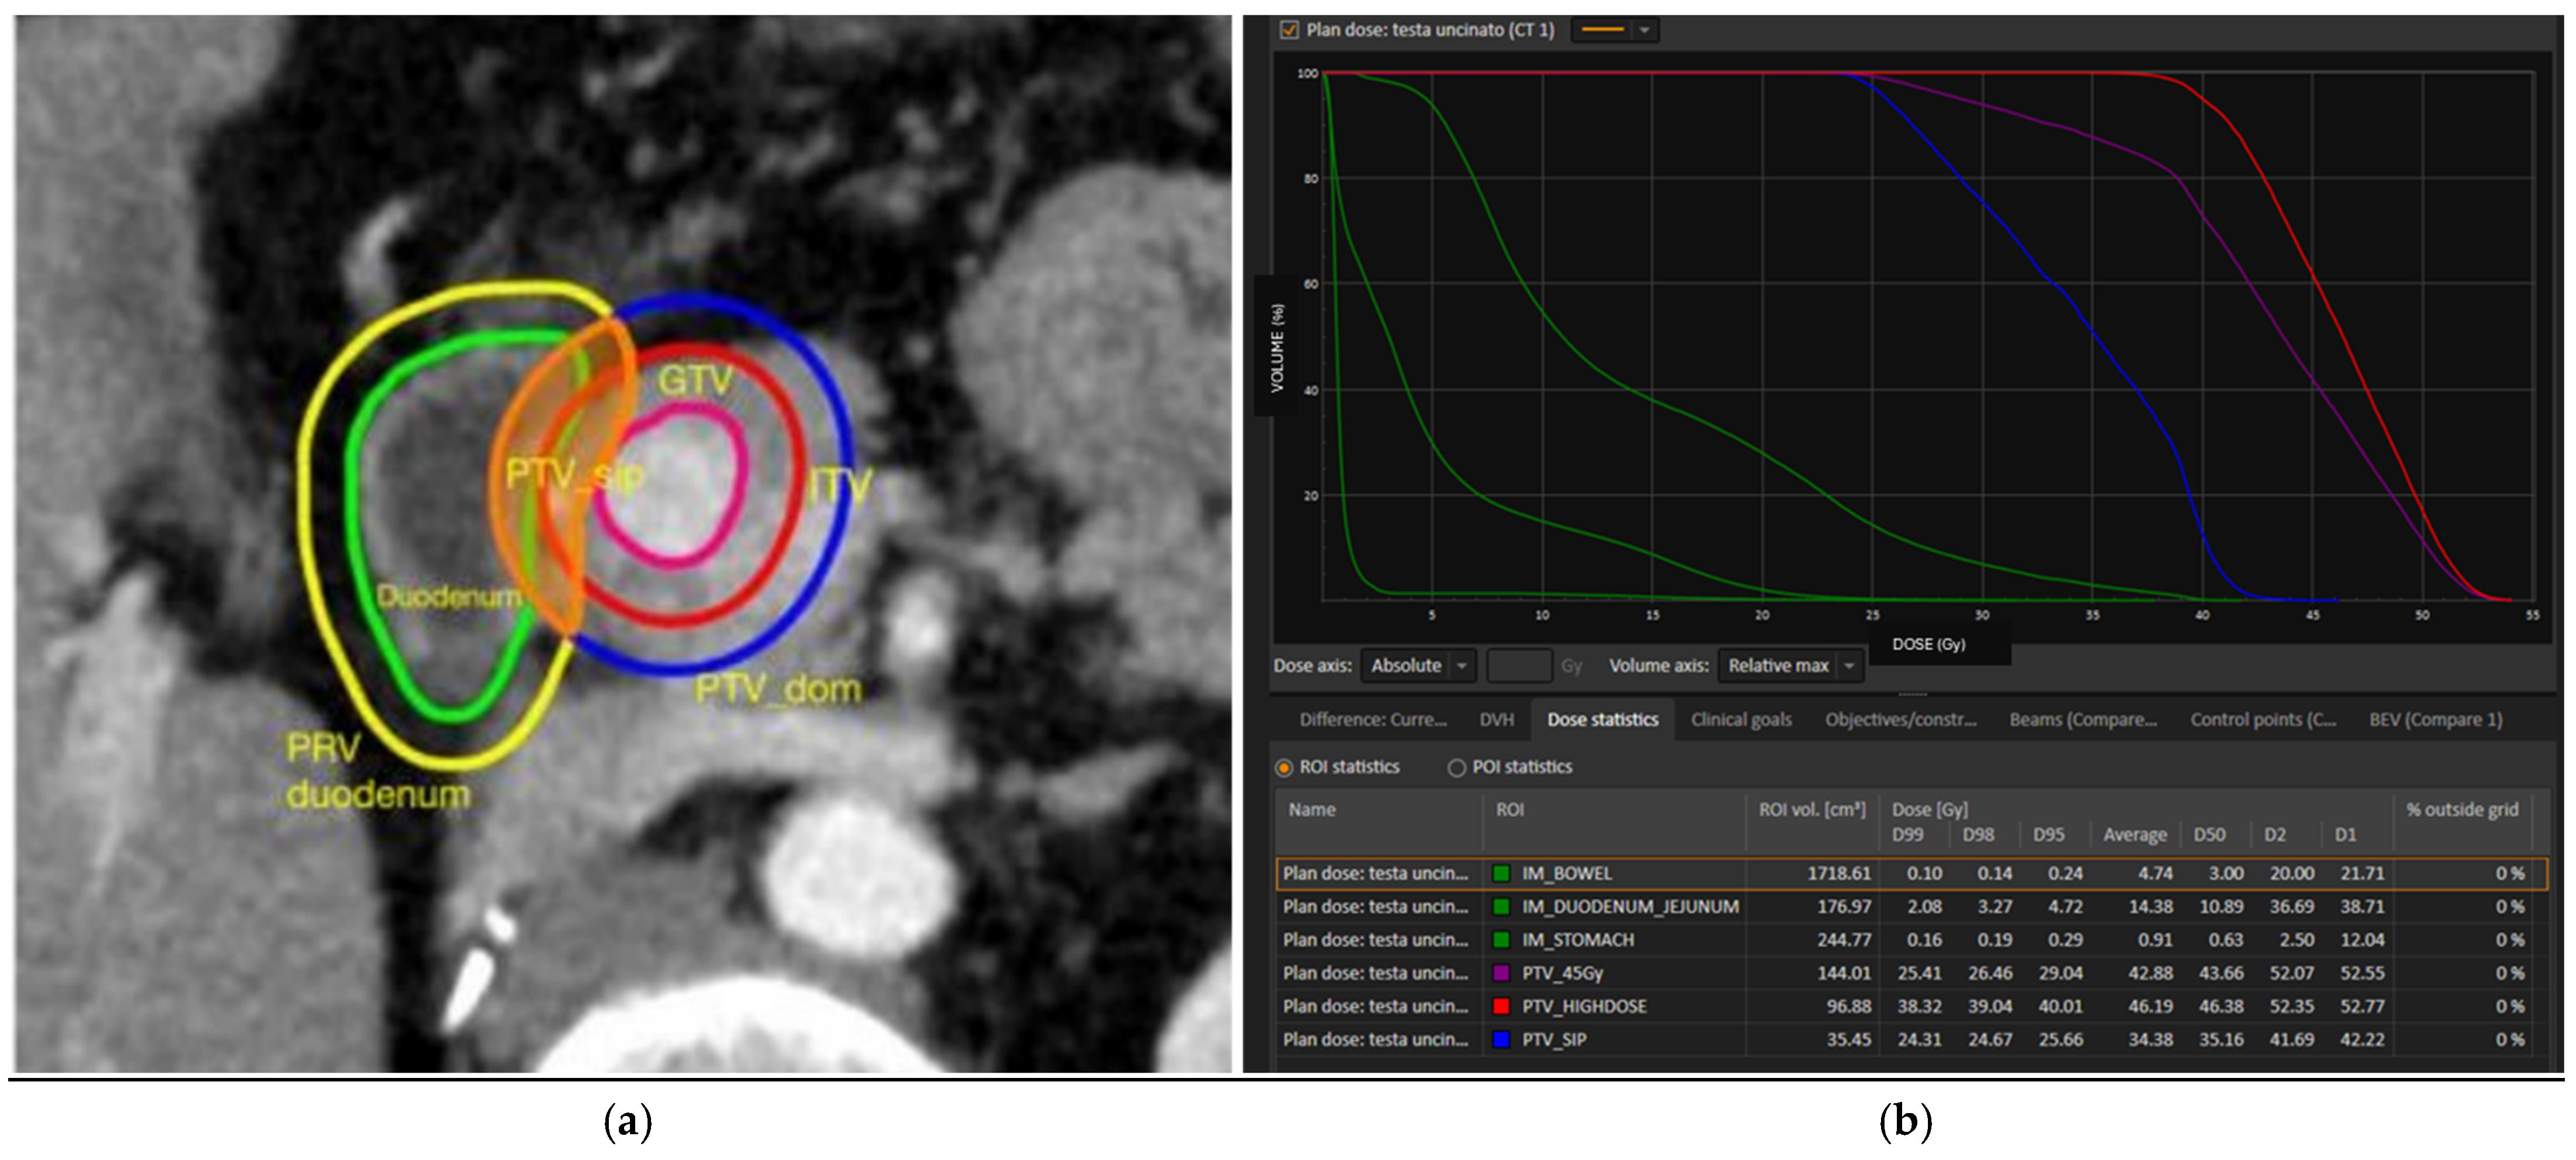

2.3. SRT Prescription, Simulation, Planning, and Delivery

2.3.3. SRT Planning